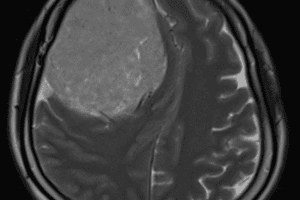

Ngày 27/10/2025, Khoa Ngoại Thần Kinh - Bệnh viện Đa khoa Trà Vinh đã phẫu thuật thành công cho bệnh nhân nữ, 46 tuổi, bị u màng não vùng thái dương đỉnh trái có kích thước khoảng 15 x 15 cm - một trong những khối u màng não lớn hiếm gặp.

Hình ảnh MRI trước mổ (trái), CT sau mổ (giữa), khối u (phải)